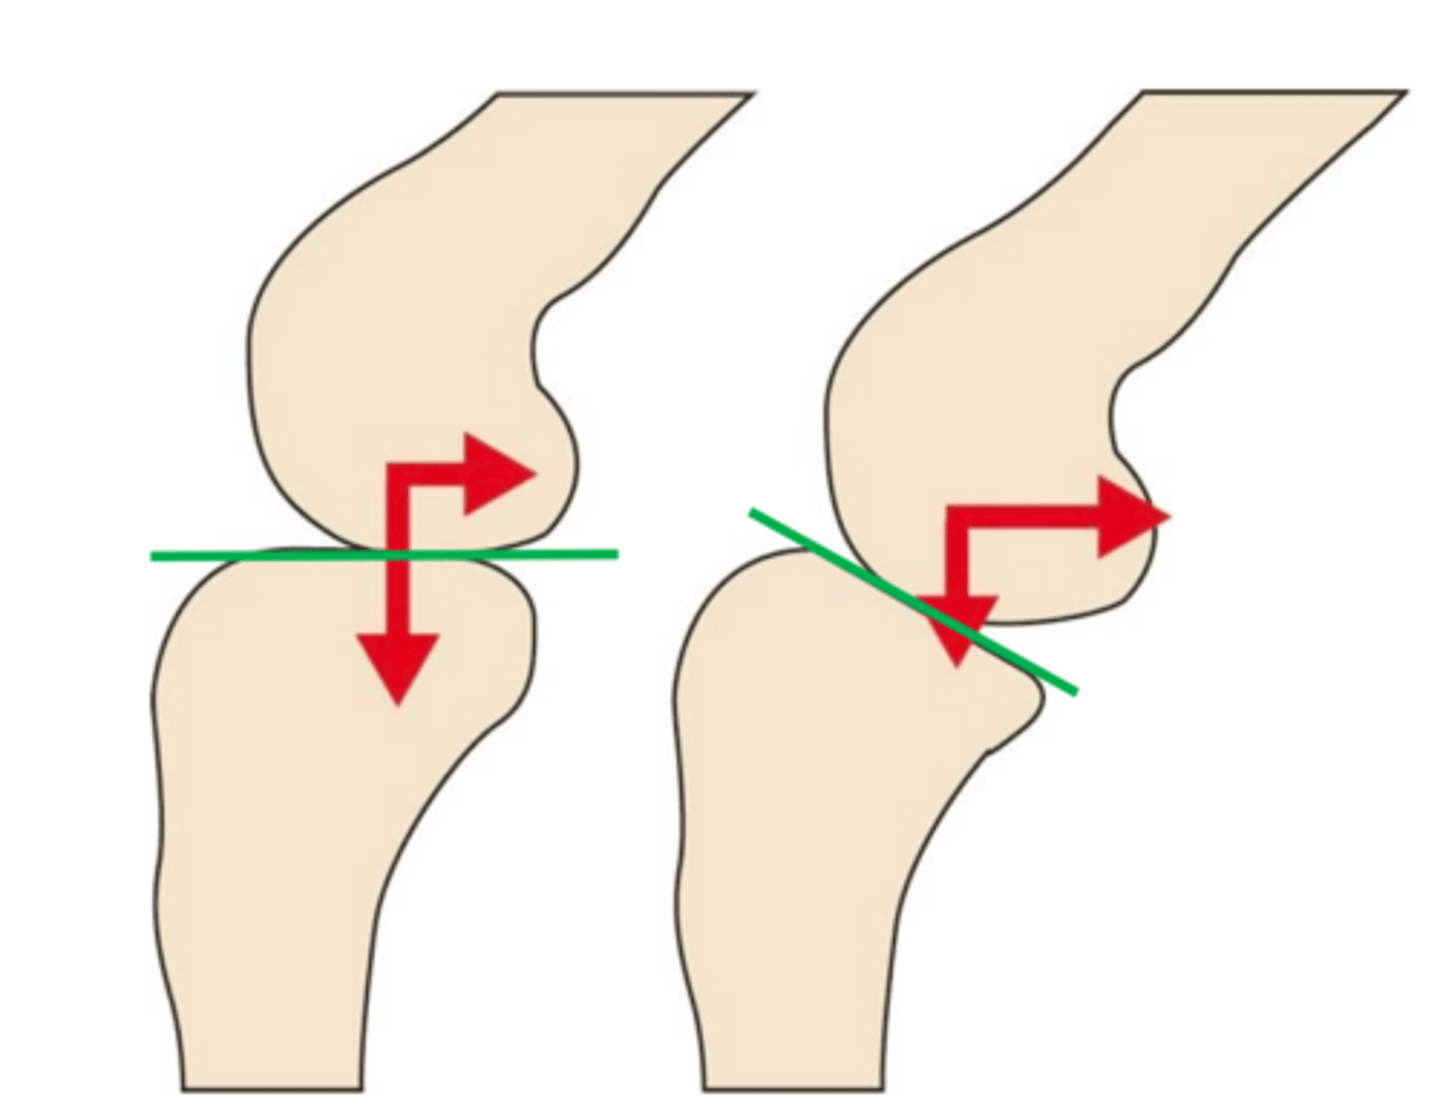

1. caudally directed slope of tibial plateau results in shear force

2. creates abnormal tibial translation in CCL deficient stifle

in terms of stifle mechanics when the tibia is loaded...

cranial tibial thrus/CTT

the shear component of compressive force is called ____ and is normally passively constrained by the CCL

slope of the tibial plateau

the CTT (cranial tibial thrust) is proportional to the ____

when the slope of tibial plateau is NOT anatomically oriented perpendicular to patellar lig, it leads to ____

cranial tibial thrust force

the vector force (parallel to patellar lig) in the tarsus + sum of wt. bearing force creates....